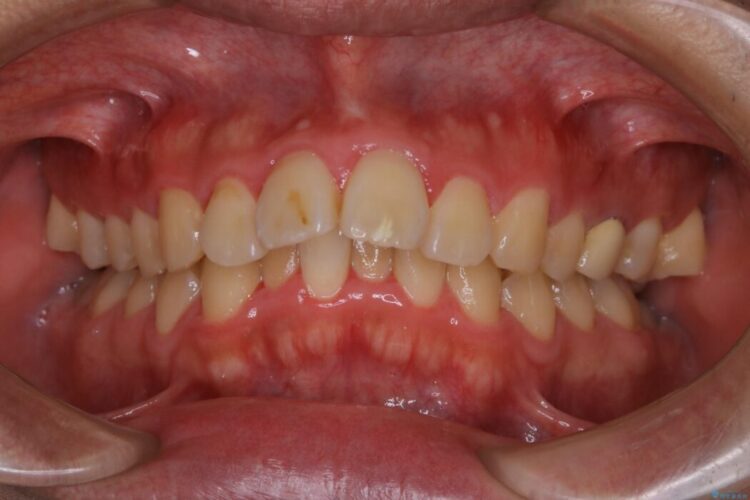

上の歯の出っ歯と下の歯のガタつきが気になるとご来院された患者様です。

出っ歯とガタつきの改善には抜歯が必要と診断し、上下左右第一小臼歯を抜歯することとしました。